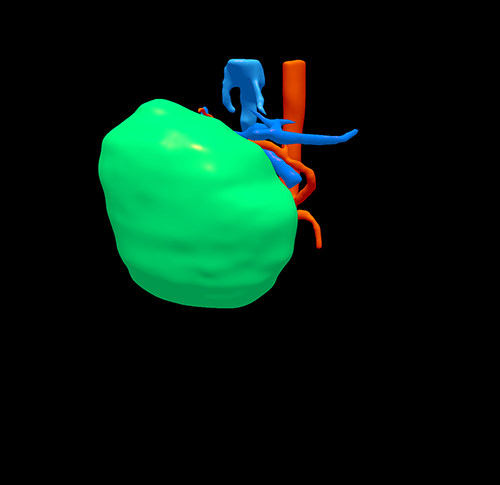

三维重建

右肝癌---右三肝切除